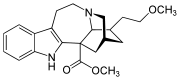

Oripavine derivatives

- Buprenorphine—partial agonist

- Dihydroetorphine

- Etorphine